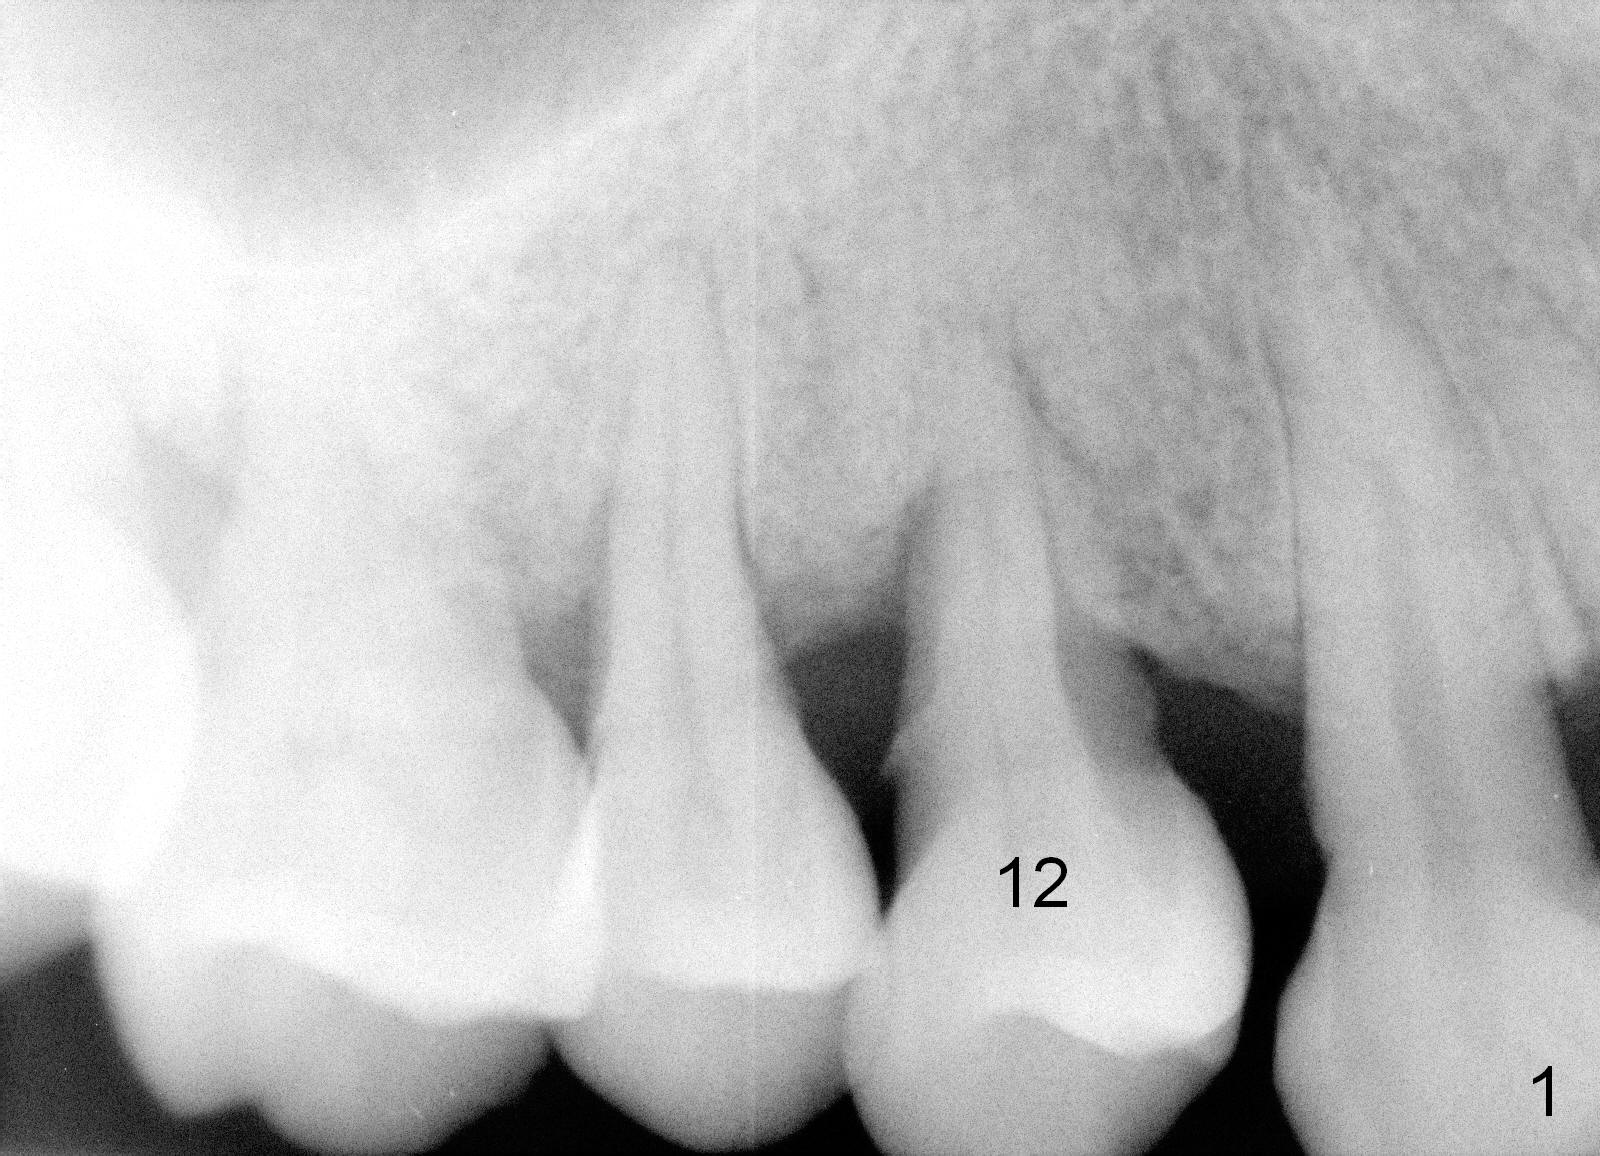

A 43-year-old lady has generalized moderate localized advanced chronic periodontits (Fig.1,2). In spite of 4 quadrant scaling & root planing, the tooth #19 develops 2 perio abscesses (Fig.4 with insertion of 2 guttae perchae); periodontal ligament spaces increases (compare Fig.2,4). It appears that the tooth is non salvageable and should be replaced with an immediate implant (Fig.5). The extraction socket will be treated with Metronidazole. A 2 mm pilot drill is used to start osteotomy in the septum (14 mm deep), followed by reamers until 3.5 mm. A 5x17 mm tap is placed to test stability. If the stability is high, place a 5.3x12 mm SM implant. If insertion torque is too high, use the corresponding drill before re-place the implant. Collagen dressing is placed in the peripheral and deep portion of the sockets, while bone graft in the top portion of the sockets (near implant threads). Use 1 or 2 amalgam carriers to deliver the graft lateral to the implant precisely so that a cover screw does not have to be placed. Next place a cemented abutment. If trajectory of the implant is correct, an abutment as large as 7.8x5(3) mm could be used (pink). Fabricate an immediate provisional. Do not over trim the margin of the provisional so that it can cover the socket completely.